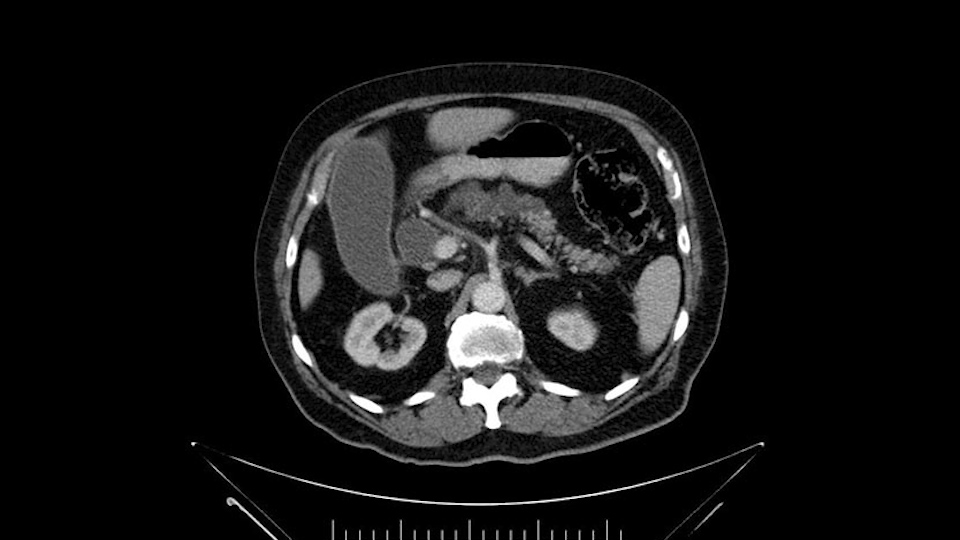

He has no liver metastases or obvious metastatic disease. On reviewing his CT scan, he has normal vascular anatomy; he has no involvement of the portal vein by the looks of it, or the superior mesenteric vein.

The only difference with him is that he has fairly extensive cystic lesions throughout his pancreas, particularly in the head and the neck. We have thought how this might affect the procedure. Likely IPMN (Intraductal Papillary Mucinous Neoplasms), and we have thought how this might affect the procedure. Is this a pancreatic adenocarcinoma rather than an ampullary cancer? The ampulla (of Vater) was abnormal on a side-viewing scope and a biopsy of this ampulla was adenocarcinoma. So I don’t think this was just a mass invading into the duodenum.

Number two, the reason why I think this IPMN might affect the procedure: it is involving the neck. So normally when we come across the neck, we would like to see a normal pancreas with a small or a large duct but you can see on the scan that this is fairly extensive duct and cystic lesion at that point. The only slowing down moment for me is really that. Coming across the pancreas, then wanting to see what that looks like and how that is going to affect my anastomosis.

He’s got a lot of adipose tissue which I know is going to make the operation more difficult. From a co-morbid point of view, after some discussion, we thought that it would be best to leave pancreas with IPMN and remove the tumor - rather than try to do a subtotal pancreatectomy and try to get all of this IPMN out - so that’s what we plan on doing.